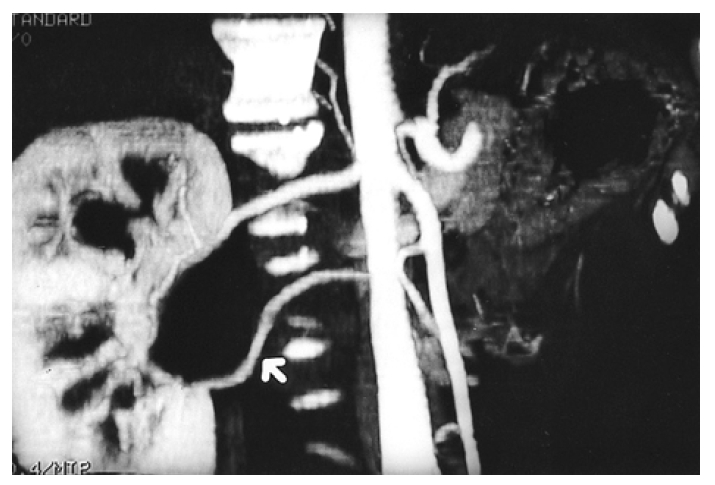

Kidney ultrasonogram showed a marked dilatation of the right pelvocalyceal system and right proximal ureter. However, the left kidney showed normal appearance. Excretory urogram revealed a marked right hydronephrosis with dilated calyces due to ureteropelvic junction obstruction (Figure 1). Computed tomography angiogram (CTA) clearly displayed the aberrant renal artery which originated from the aorta below the normal right renal artery (Figure 2). A source image of magnetic resonance angiogram (MRA) also showed a severe hydronephrosis of the right kidney and smooth obstruction of the right ureteropelvic junction due to extrinsic compression by an aberrant renal artery which originated from the aorta, crossing anteriorly to the ureteropelvic junction (Figure 3). Retrograde pyelogram demonstrated linear indentation of the proximal ureter (Figure 4). Tc-99m DTPA renal scan revealed a markedly delayed excretion of the right kidney. After furosemide infusion, the delayed right kidney excretion was somewhat improved (Figure 5).

Figure 2.

CTA with a maximum intensity projection technique demonstrates two renal arteries originating from the aorta. An inferior aberrant artery (arrow) is crossing over the ureteropelvic junction.